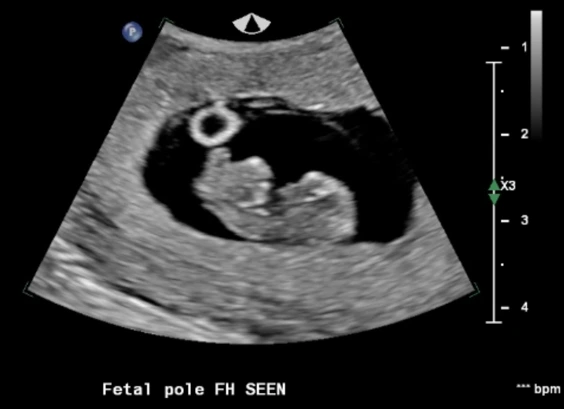

주변에 아이가 생기지 않아 고생하는 사람들을 보긴 했지만 남의 일이라는 생각이 컸고, 자연임심으로 아이들을 낳은 친구들이 더 많았기에 나도 피임을 하지 않으면 어렵지 않게 아이가 생길 거라고 생각했다. 그러나 한 달 두 달이 지나도 소식이 없자 자연임신이라는 것이 쉬운 게 아니라는 것을 깨달았고 좀 더 집중해서 아이를 갖으려 노력한 결과, 세 달째가 됐을 때 마법처럼 생리가 멈추었다. 임신테스트기에 두 줄을 확인했을 때 심장이 두근거리고 호흡이 빨라졌다. 진짜인가 싶어 한동안 두줄을 뚫어져라 쳐다보고 있었다. 마이클은 이 소식을 듣고는 나를 안아주며 너무 좋다고 기뻐했다. 임신을 하고 나서 처음 몇 주 동안은 실감이 전혀 나지 않다가 12주 차 초음파에서 아기의 심장소리를 듣고 그제야 내 뱃속에 생명이 자라고 있다는 것을 느낄 수 있었다. 구토를 하는 입덧은 없었지만 4시간에 한 번씩 밥을 먹어야만 메슥거림이 줄어들었고 소화가 너무 안 돼서 항상 위가 불편했다. 먹지 않아도 메슥거리고 그렇다고 먹으면 또 소화가 안 돼서 아프고, 이도저도 하기 힘든 상태가 2달가량 지속됐다.